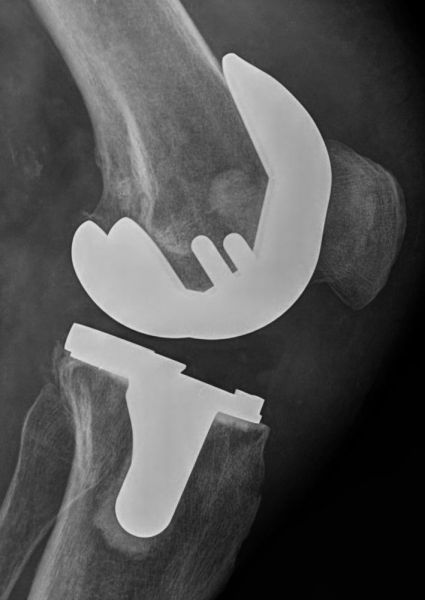

4. Severe osteoarthritis of the left knee in an 80-year-old male.

Treatment: Total knee arthroplasty

I. Before the surgery, anteroposterior x-ray left knee shows the severe osteoarthritis at the medial side II. One month down the line from the operation, lateral x-ray of the knee III. One month down the line from the operation, anteroposterior x-ray of both knees in a standing position